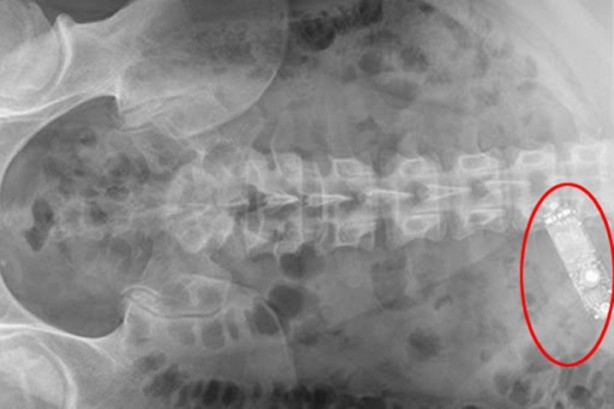

CEP TELEFONU Ürdün'ün başkenti Amman'da yaşanan bu ilginç olayda Hanan Mahmoud Abdul Karim isimli 36 yaşındaki vatandaş, özel bir hastanede sezaryenle doğum yaptı. Doğumun ardından bebeğiyle birlikte evine dönen kadın, karnında sürekli titreyen bir cisim olduğunu fark ettiğinde vakit kaybetmeden kocasıyla birlikte hastaneye gitti. Sonra ne oldu dersiniz? Hastanede hızlıca röntgeni çekilen Mahmoud Abdul Karim'in karnının içinde doğum ameliyatı sırasında unutulduğu düşünen bir cep telefonu çıktı.